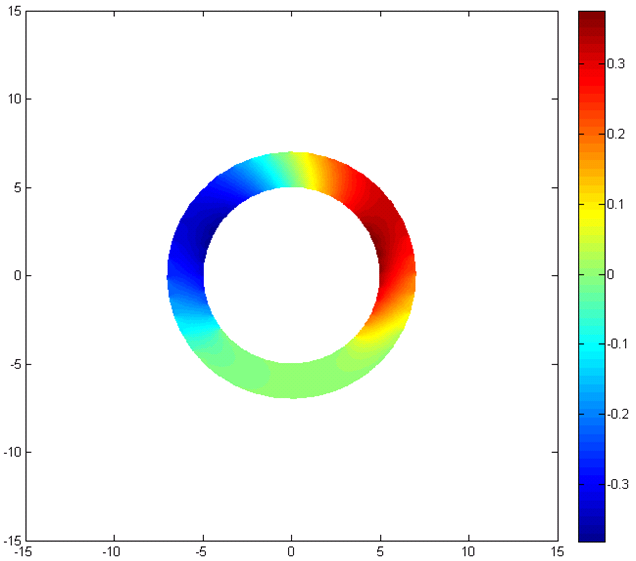

After the analysis with ANSYS, the proposed model should be implemented and the results should be compared and verified with the results of ANSYS analysis. At first the inner and our contours of the ring is determined. Then, after setting the boundary conditions, the governing equation of deformation is solved using FEM and the deformation maps are created. All the code is implemented in MATLAB.

Fig. 4 represent the results of the proposed method for both horizontal, vertical and absolute displacement. To better be able to compare the results, the ring is divided into 16 sub-regions and the results of ANSYS and MATLAB implementations are compared. Fig. 5 shows the average displacement in each region for 10 iterations of pressure increment for both ANSYS and proposed method. Based on the provided results, it can be seen that the proposed model is consistent with the results of ANSYS, even in regions with low mobility (regions 11, 12, 13 and 14).